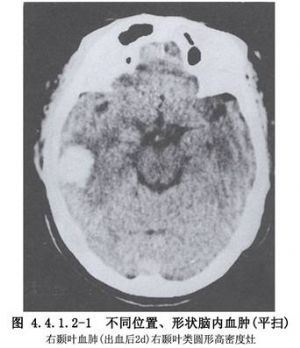

皮质下血肿或脑叶血肿在高血压性脑出血中约占15%,以额叶、颞叶、顶叶为多见。应注意与动静脉畸形或其他原因所致的脑内血肿相鉴别。CT扫描可以确定其部位和大小。如血肿<30ml,临床症状稳定,可行保守治疗观察,许多病人可吸收自愈。但如观察过程中症状加重,或血肿量在30ml以上,颅高压症状明显,应考虑手术治疗。此类血肿死亡率较低,早期清除血肿,有助于脑功能恢复(图4.4.1.2-1)。